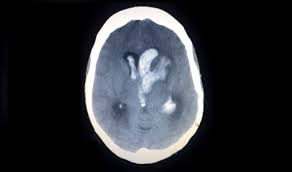

Home › cara mengatasi pembekuan darah › cara mengencerkan darah beku di kepala › cara mengobati darah beku gumpalan darah di kepala akibat pembekuan di wilayah lain. Akibat kejadian itu, jibob atau nama sebenarnya mohd hamizi hashim kemudiannya dimasukkan ke wad unit rawatan rapi (icu) neurology hospital kuala lumpur (hkl), kerana darah beku di kepala. Pemeriksaan doktor mendapati ada ketulan darah beku di kepala kerana kekurangan oksigen, katanya. Cedera kepala cedera kepala juga menjadi penyebab penggumpalan darah di otak dan juga menimbulkan gejala gegar otak. Dear heril, benturan pada kepala dapat menimbulkan trauma atau cedera, serta perdarahan pada jaringan otak sehingga akhirnya timbul gangguan fungsi otak baik. Darah beku di kuku atau dikenal dalam istilah medis sebagai hematoma subungual merupakan kondisi yang dapat terjadi pada setiap orang. Selain trephination, cara lain mengobati darah beku di kuku adalah kauter. Sedangkan darah beku di kepala yang terjadi pada bagian pusat bicara, maka pasien dapat mengalami gangguan dalam berbicara. Bahkan pembekuan yang terjadi di kepala ini dapat mengancam nyawa jika tidak segera ditangani. Darah perawan bulan madu movie. Gula darah tinggi atau dikenal dengan hiperglikemia adalah kondisi ketika kadar glukosa di dalam darah mengalami kenaikan. Ini pengalaman sendiri.utk yg tertarik mencoba dg cara ini bisa hub ane. Contextual translation of darah beku didalam kepala into english.

Cedera kepala cedera kepala juga menjadi penyebab penggumpalan darah di otak dan juga menimbulkan gejala gegar otak. Kalau telah lewat beberapa waktu di luka sementara saya tidak tahu, apakah telah hilang atau belum? Bahkan pembekuan yang terjadi di kepala ini dapat mengancam nyawa jika tidak segera ditangani. Jadi apa penyebab darah menjadi beku? Pembekuan darah merupakan proses alami yang mengizinkan darah membentuk gumpalan sel darah dan fibrin untuk menghentikan pendarahan ketika pembuluh darah sobek atau rusak. Pengumuman terbaru itu menyusul laporan yang juga terbaru mengenai kejadian langka pembekuan atau penggumpalan darah pada sebagian kecil penerima paul ehrlich institute, regulator vaksinasi di jerman, menyebut seluruhnya terdata 31 kasus penggumpalan darah di kepala atau cerebral sinus. Darah perawan bulan madu movie. Gula darah tinggi atau dikenal dengan hiperglikemia adalah kondisi ketika kadar glukosa di dalam darah mengalami kenaikan.

Sakit kepala yang berkepanjangan merupakan gejala gumpalan darah di kepala yang sering diabaikan. Cedera kepala cedera kepala juga menjadi penyebab penggumpalan darah di otak dan juga menimbulkan gejala gegar otak. Dear heril, benturan pada kepala dapat menimbulkan trauma atau cedera, serta perdarahan pada jaringan otak sehingga akhirnya timbul gangguan fungsi otak baik. Kauterisasi bedah ini memanfaatkan alat berbentuk kawat logam panas atau laser. Kalau telah lewat beberapa waktu di luka sementara saya tidak tahu, apakah telah hilang atau belum? Oleh sebab itu, cermati gejala kondisi hiperglikemia dan cara mengatasinya. Sekilas mengenai pembekuan darah di kepala. Terjatuh serta tertusuk benda tajam seperti pisau merupakan. Jika terjadi pembekuan darah di kepala sebaiknya di kompres dengan air hangat krn mengompres dengan air dingin hanya akan membuat pembuluh darah semakin sebaliknya jika luka memar, maka di kompres dengan ir dingin agar pembuluh darah membeku dan darah berhenti mengalir. Mengobati darah beku di kuku dengan cara melubangi bagian kuku dengan menggunakan kawat logam yang panas. Sedangkan darah beku di kepala yang terjadi pada bagian pusat bicara, maka pasien dapat mengalami gangguan dalam berbicara. Pemeriksaan doktor mendapati ada ketulan darah beku di kepala kerana kekurangan oksigen, katanya. Apabila ibu saya bertempur dengan saya, ibu saya.